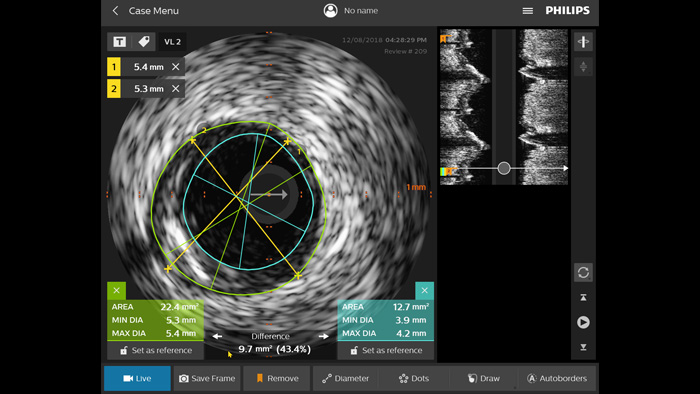

Otimize os desfechos de pacientes utilizando um critério de IVUS padronizado. Em comparação com o uso isolado de ICP guiado por angiografia em todos os pacientes atendidos, o ULTIMATE demonstrou que o ICP guiado por IVUS reduz significativamente a revascularização da lesão alvo (TLR) impulsionada clinicamente. Essa vantagem foi mantida ao longo de três anos. Foram observadas apenas 1,6% de falha do vaso alvo (TVF) após 12 meses e 4,2% de TVF após 3 anos quando os critérios ideais de ICP guiada por IVUS foram cumpridos.